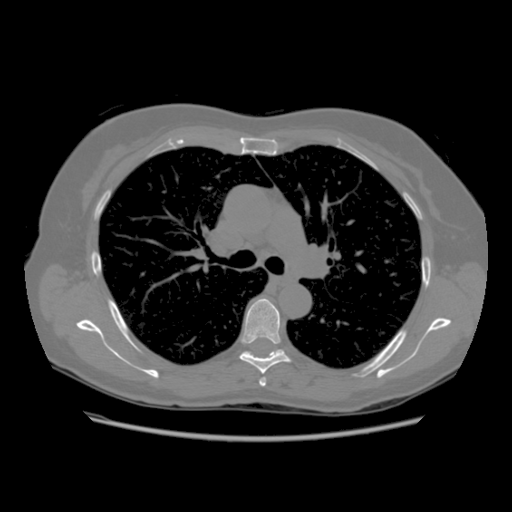

4.3 Few-View CT Reconstruction

In this section, the reconstruction performance of our proposed framework under few-view conditions will be tested. For the parallel-beam and fan-beam geometry, the number of views increases from to , uniformly distributing from to and to respectively. Such settings provide a complete benchmark of reconstruction performance, ranging from extremely sparse to relatively complete, full-view CT reconstruction. The experiment results are shown in Fig.5. Additionally, the ground truth, few-view ( views), and full-view ( views) CT reconstruction results of different methods are shown in the first and third rows of Fig.7 (parallel-beam, LIDC-IDRI dataset), and Fig.8 (fan-beam, LIDC-IDRI dataset).

4.4 Limited-Angle CT Reconstruction

To test the proposed framework’s performance on limited-angle reconstruction, we redo the experiment in the above section with the angular range changing from to for parallel-beam geometry and to for fan-beam geometry, one projection per degree. The experiment results are shown in Fig.6. Also, the ground truth and the limited-angle CT reconstruction results of different methods are shown in the row of Fig.7 (parallel-beam, LIDC-IDRI dataset), and Fig.8 (fan-beam, LIDC-IDRI dataset).

(a) Ground Truth

43.87dB

(b) ASD-POCS

47.96dB

(c) RBP-DIP

34.46dB

(d) DIP

26.63dB

(e) MED50

29.03dB

(f) RED-CNN